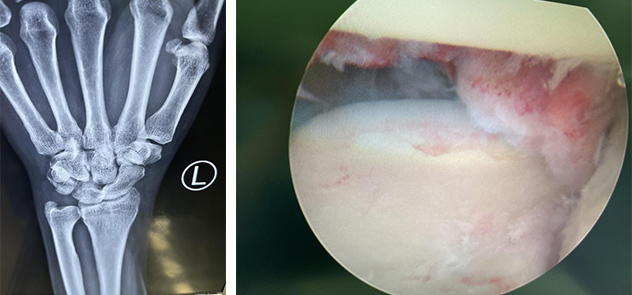

术前(左图)术中清除滑囊,关节腔清扫(右图)

第二天,齐主任、方杰、吴衡手术团队为张大伯进行了腕关节镜下月骨脱位复位内固定术。术中,手术团队在关节镜下进行关节腔清扫,清除滑膜、瘢痕组织,松解韧带,月骨复位内固定,手术非常顺利。